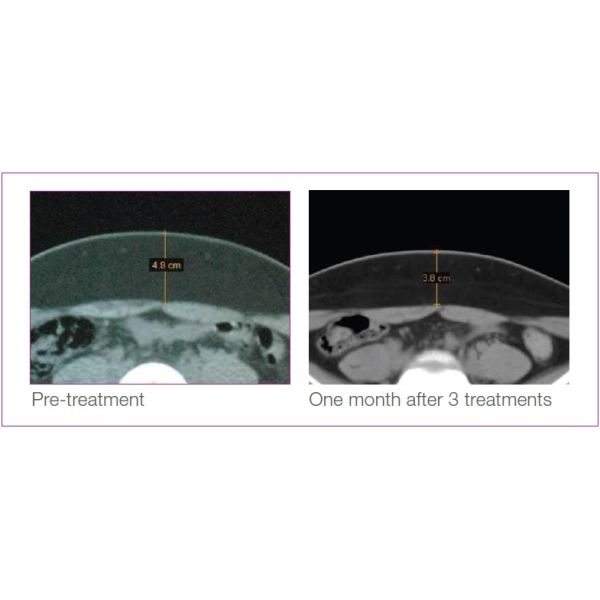

The HIFUSHAPE System is the first and only FDA cleared, non-invasive body shaping device that uses pulsed, focused ultrasound to mechanically (non-thermally) and selectively destroy fat cells at a designated focal point in the subcutaneous fat tissue without harming the skin, blood vessels, nerves or connective tissue, demonstrating measurable results in as little as 2 weeks.

Focused:Ultrasound energy is designed to precisely converge into a confined focal volume, targeting onlysubcutaneous fat at a controlled depth.